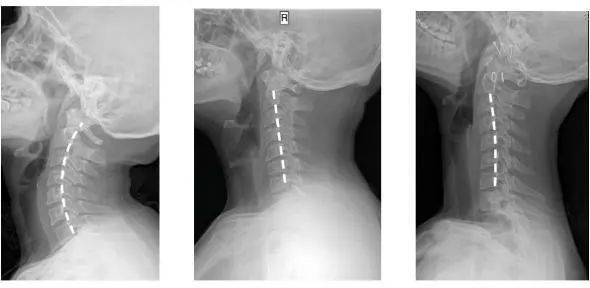

人正常的颈椎是有弧度的

大约是前凸30-45°

但随着颈椎长时间承受着巨大压力

过于疲劳态势

于是弧度就

逐渐退化 变直 甚至反弓

第一张为正常生理曲度,第二张曲度变直,第三张是反向弯曲

前凸的颈椎曲度被改变

结果就是引发椎间盘突出

造成对血管和神经的压迫

肩膀和脖子容易酸痛僵硬

这已是颈椎病的初期症状